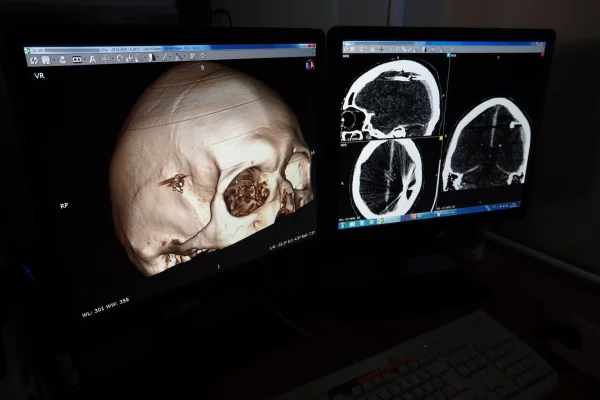

В Барнауле нейрохирурги «Краевой клинической больницы скорой медицинской помощи» спасли пациента, который сутки ходил с пулей в голове. Компьютерная томография показала, что у него в головном мозге находятся множественные металлические объекты.

Пациент попал в больницу только после потери сознания. У него отсутствовала двигательная активность в правой стороне тела. Врачи приняли решение об оперативном вмешательстве и извлечении инородных тел из головного мозга пациента.

Во время операции, продолжавшейся 2,5 часа, врачи-нейрохирурги Владислав Стеблецов и Абдужомил Отомуротов удалили костные фрагменты, образовавшиеся из-за удара пули, части повреждённого головного мозга и осколков, оставшихся в правой теменной области, извлекли пулю из вещества головного мозга и устранили гематому, возникшую после её попадания. Состояние пациента удалось стабилизировать и предотвратить возможные осложнения, сообщили в ККБСМП.